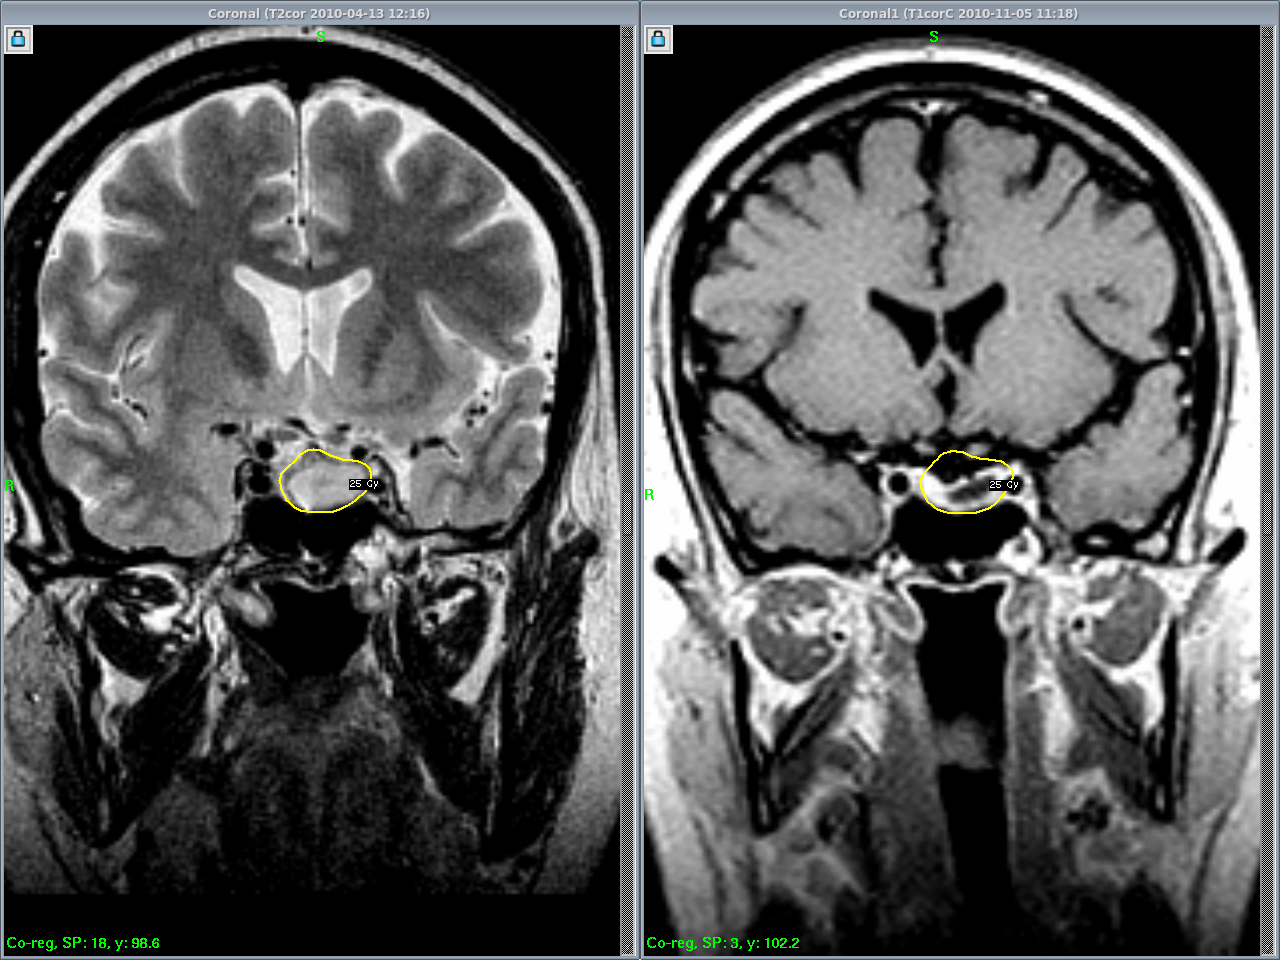

Микроаденома симптомы

Микроаденома симптомы 112 фото